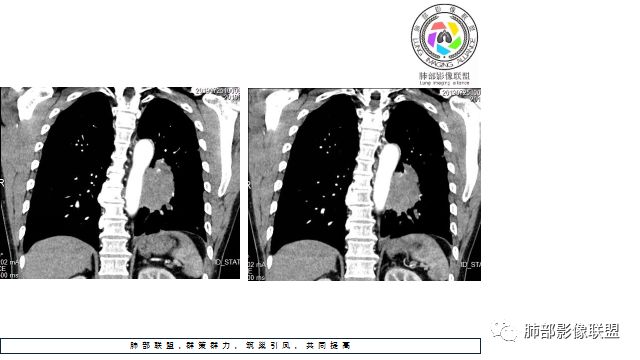

1.左下肺门区巨大肿块,支气管显示不清,轻度阻塞性炎症,没有明显肺不张,提示管腔受压狭窄可能性大于堵塞,这较少见于鳞癌。

2.病灶边缘光滑,未见明显分叶、毛刺,未见明显强化,这符合腺癌影像学特点,却符合神经内分泌癌表现。

3.病灶内密度均匀,轻到中度均匀强化,大病灶未见明显液化坏死区及空洞,不符合鳞癌而符合小细胞肺癌特点。

4.病灶内有肺动脉走形,血管局部受压,未见破坏,病灶乏血供,呈血管包埋或血管造影征;侵袭性力强及破坏力弱、血管漂浮都符合SCLC,所以鳞癌的可能性也不大。

5.左肺门块影或淋巴结肿大,竭力挤兑肺门血管结构,呈冰冻肺门;有时候SCLC可以单独呈现冰冻肺门,而没有没有冰冻纵隔。

7.须特别注意的是,肺门区的融合块影,不排除它可能仅仅为转移淋巴结。